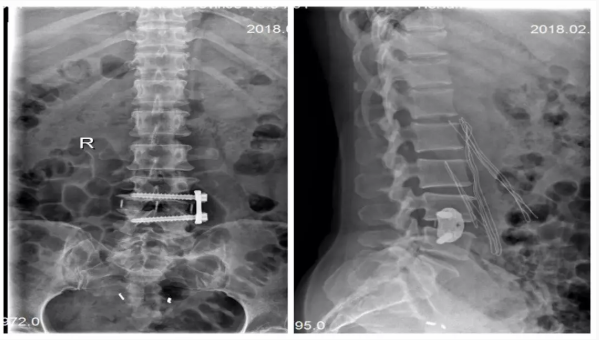

术前

术后

XLIF手术采用单一小切口腹膜后入路完成椎管内间接减压、并进行可靠融合,无需后路内固定,为微创融合提供了又一条解决方案。该技术优势在于允许最大面积与高度的椎间融合器植入,无需剥离牵拉腹膜后大血管与神经,经腹膜后腰大肌肌纤维侧方入路,避免了对腹膜、大血管及神经的过度牵拉及剥离。更为关键的是,XLIF不必切除椎板、关节突关节等维持脊柱结构,避免术后腰背部僵硬疼痛等传统手术并发症。